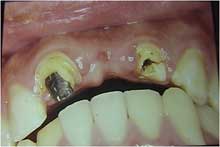

前歯ブリッジ破損症例、口腔内写真

術前